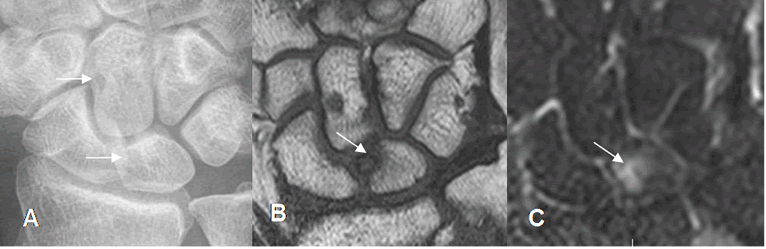

Fig 88 A. Impactación del carpo.

A: Rx AP. Imágenes radiolúcidas en los huesos grande y semilunar, por lesiones osteocondrales.

B: RM coronal en T1 y B: RM coronal en STIR. Lesión osteocondral hipointensa en T1 e hiperintensa en STIR, en la parte superomedial del semilunar, por pinzamiento grandelunado.